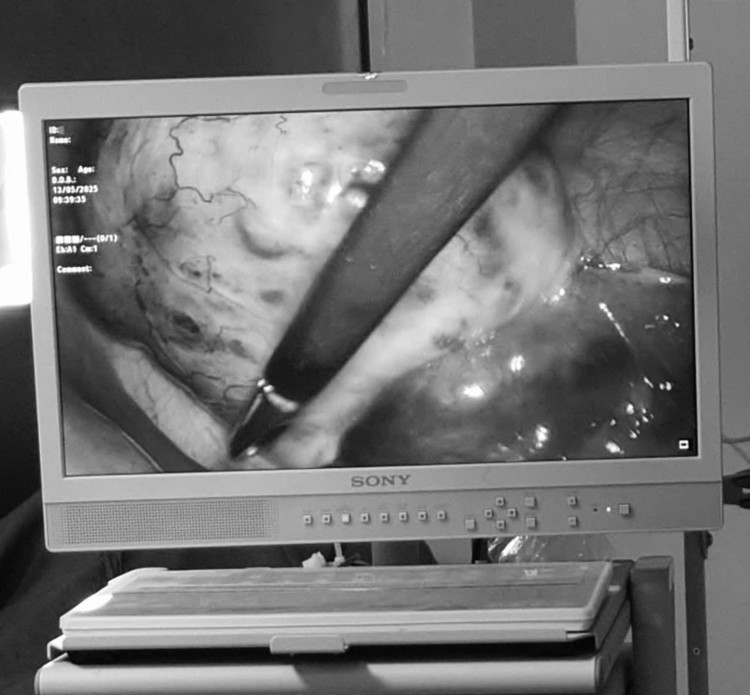

U buồng trứng xoắn trên hình ảnh nội soi - Ảnh BVCC

Bước vào cuộc mổ, các bác sĩ ghi nhận khối u bì đường kính khoảng 5 cm tại buồng trứng phải, cuống u bị xoắn 3 vòng, vòi trứng phù nề, bề mặt buồng trứng có dấu hiệu hoại tử. Ê-kíp nhanh chóng tiến hành tháo xoắn, bóc tách khối u cẩn trọng, bảo tồn tối đa mô lành của buồng trứng.